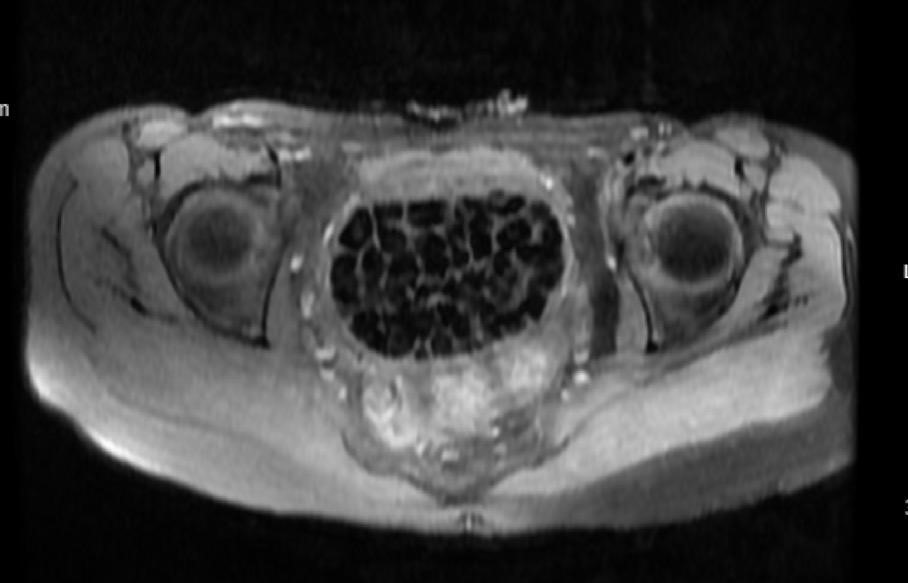

Genç kızın uzun süredir devam eden karın ağrısı olduğunu söyleyerek sözlerine başlayan Jinekolojik Onkoloji Uzmanı Op. Dr. Emin Erhan Dönmez, "Mesane taşları olduğu düşünülerek daha büyük bir hastaneye refere edilmiş. Aramızda mini bir konsey yaparak muayene ettik. Vajen bir hazne görevi görerek orada durağan bir idrar, uzun süre beklediği için idrar içindeki minerallerde çökerek taşlar oluşmuş. Mesanedeki idrarın vajene akmış olabileceği ve vajende göllenen idrar nedeniyle taşların burada oluşacağını düşündük, ameliyatımızı planladık. Ameliyata tanı amaçlı girmiştik, sistoskopi (Mesane gibi idrar yollarını kapsayan kısımlardaki rahatsızlıkların teşhis ve tedavisinde kullanılan endoskopik bir yöntem) dediğimiz ameliyatı Erkan Hocam ile birlikte gerçekleştirdik. Önce mesaneyi bir görüntüledik, mesane tabanına yaklaşık 2-3 cm’lik bir alandan vajene fistülize olduğunu gördük. Mesaneden vajene geçtiğimiz esnada tüm vajenin taşlarla dolu olduğunu gördük. Tanı amacıyla girdiğimiz ameliyatta her şey de olağan gittiği için tedaviye geçtik. Taşların çıkabileceği kadar bir genişlik sağladık. Daha sonra yaklaşık en büyüğü 2,5 cm boyutlarında olan, irili ufaklı 287 tane taşı ameliyat esnasında çıkarmış olduk. Taşların tekrarlamaması için idrarın göllenmemesi, en azından dışarıya rahatça boşalabilmesi için vajinal rekonstrüksiyonu sağladık. Ameliyatta da herhangi bir problem yaşamadık. Literatürü Erkan Hocam ile birlikte değerlendirmiştik. Primer olarak vajende birikmiş olan bu kadar çok sayıda taşla ilgili bir makale görmedik, rastlamadık" dedi.